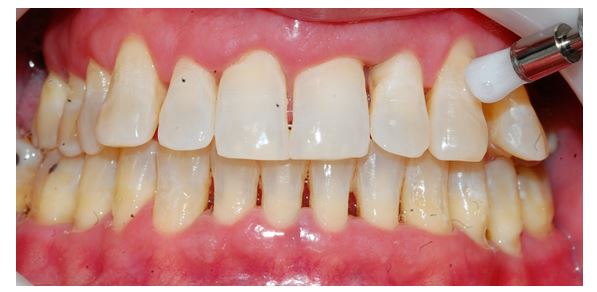

The patient’s right and left sides were randomly selected to use one of the prophylaxis dental protocols: REFIX dental gel associated with calcium (RDGCa) (experimental) or Pumice Stone (PS) (control). The vestibular faces of the teeth 13, 14, and 15 were treated with RDGCa, (Figure 2) and the vestibular faces of the teeth 23, 24, and 25 were treated with PS (Figure 3). The applications involved prophylaxis with the products using dental polishing brush duration of 10 seconds in each tooth surface.

Figure 2: REFIX dental gel associated with calcium application from the authors’ source.